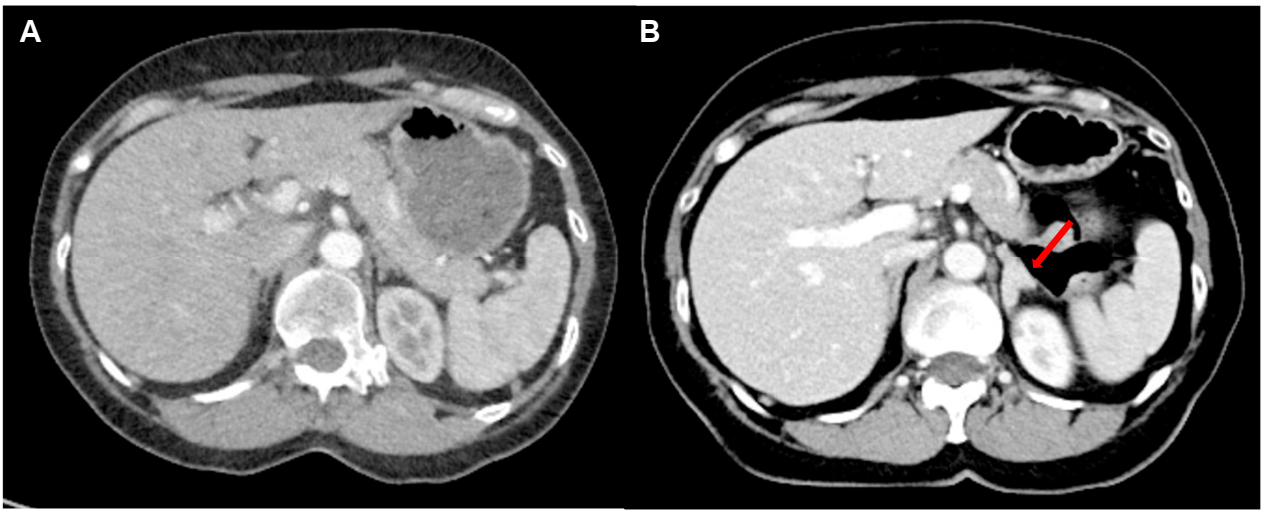

• 腹部增强 CT(图 1B):偶然发现左侧肾上腺弥漫性增厚(形态仍保留肾上腺轮廓),与 5 年前 CT(图 1A,肾上腺形态正常)对比为新发异常;

图1 腹部增强 CT